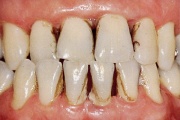

Krooniline parodontiit

Parodontiit